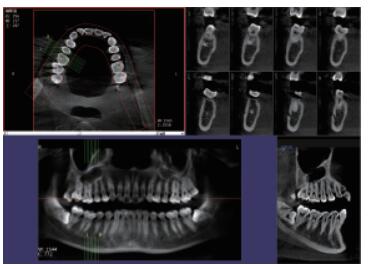

普愛口腔CT設(shè)備圖像質(zhì)量高產(chǎn)品說明:

運(yùn)用口腔CT進(jìn)行檢查可以大大提高口腔科臨床水平。以普愛醫(yī)療口腔CT為例,(它)可用于口腔種植、正畸、牙體牙髓、牙周、顳下頜關(guān)節(jié)、頜面外科及其他診斷需求,它有掃描速度快、成像速度快、操作軟件專業(yè)性強(qiáng)等優(yōu)點(diǎn),它可以輔助各種臨床診斷與治療??谇籆T產(chǎn)品特點(diǎn):

CMOS成像質(zhì)量優(yōu)

采用高端平板探測器,分辨率高、圖像質(zhì)量優(yōu)。

三維重建任意斷層

專有三維重建算法,可提供任意位置高清斷層影像。

高清口腔全景影像

通過三維容積影像,提取高清口腔全景影像。

專有圖像處理軟件

專有圖像校正技術(shù),去除金屬偽影,提高圖像分辨率。

多平面組合重建

可同時(shí)觀察軸向面、冠狀面和矢狀面圖像,方便臨床診斷。